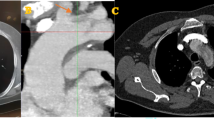

344 CT scans were studied. We measured the distances from the apex to the ascending and descending aorta, the curvilinear length of the entire arch, that of the segment, including bifurcations of supra-aortic vessels, and the angle, height, and shift of the arch.

In men, the arch was significantly longer (146.2 vs 122.8 mm; p < 0.001), higher (49.3 vs 40.1 mm, p < 0.001), and wider transversely (83.6 vs 73.3 mm; p < 0.001) than in women. The average men’s arch also had a more acute angle at the apex (79.7° vs 83.7° p < 0.001). Neither morphology nor age influenced the winding angle around the mediastinum. Aging was accompanied by deflection and extension of the aortic arch, which grew more anteroposteriorly (6.1 mm/10 years in men) than vertically (2.5 mm/10 years in men), while the apex moved towards the rear of the arch. The ascending aorta was the only curvilinear length unaffected by age, whereas the supra-aortic trunks parted from each other.